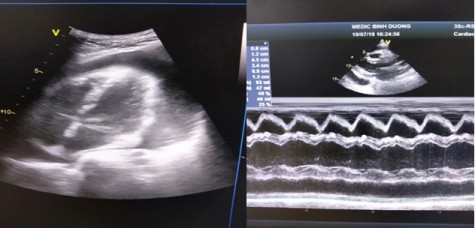

Tràn dịch màng tim có đe dọa tính mạng không?

Tràn dịch màng tim, một khái niệm không còn xa lạ đối với các bác sĩ hoặc những người hoạt động trong lĩnh vực y học.